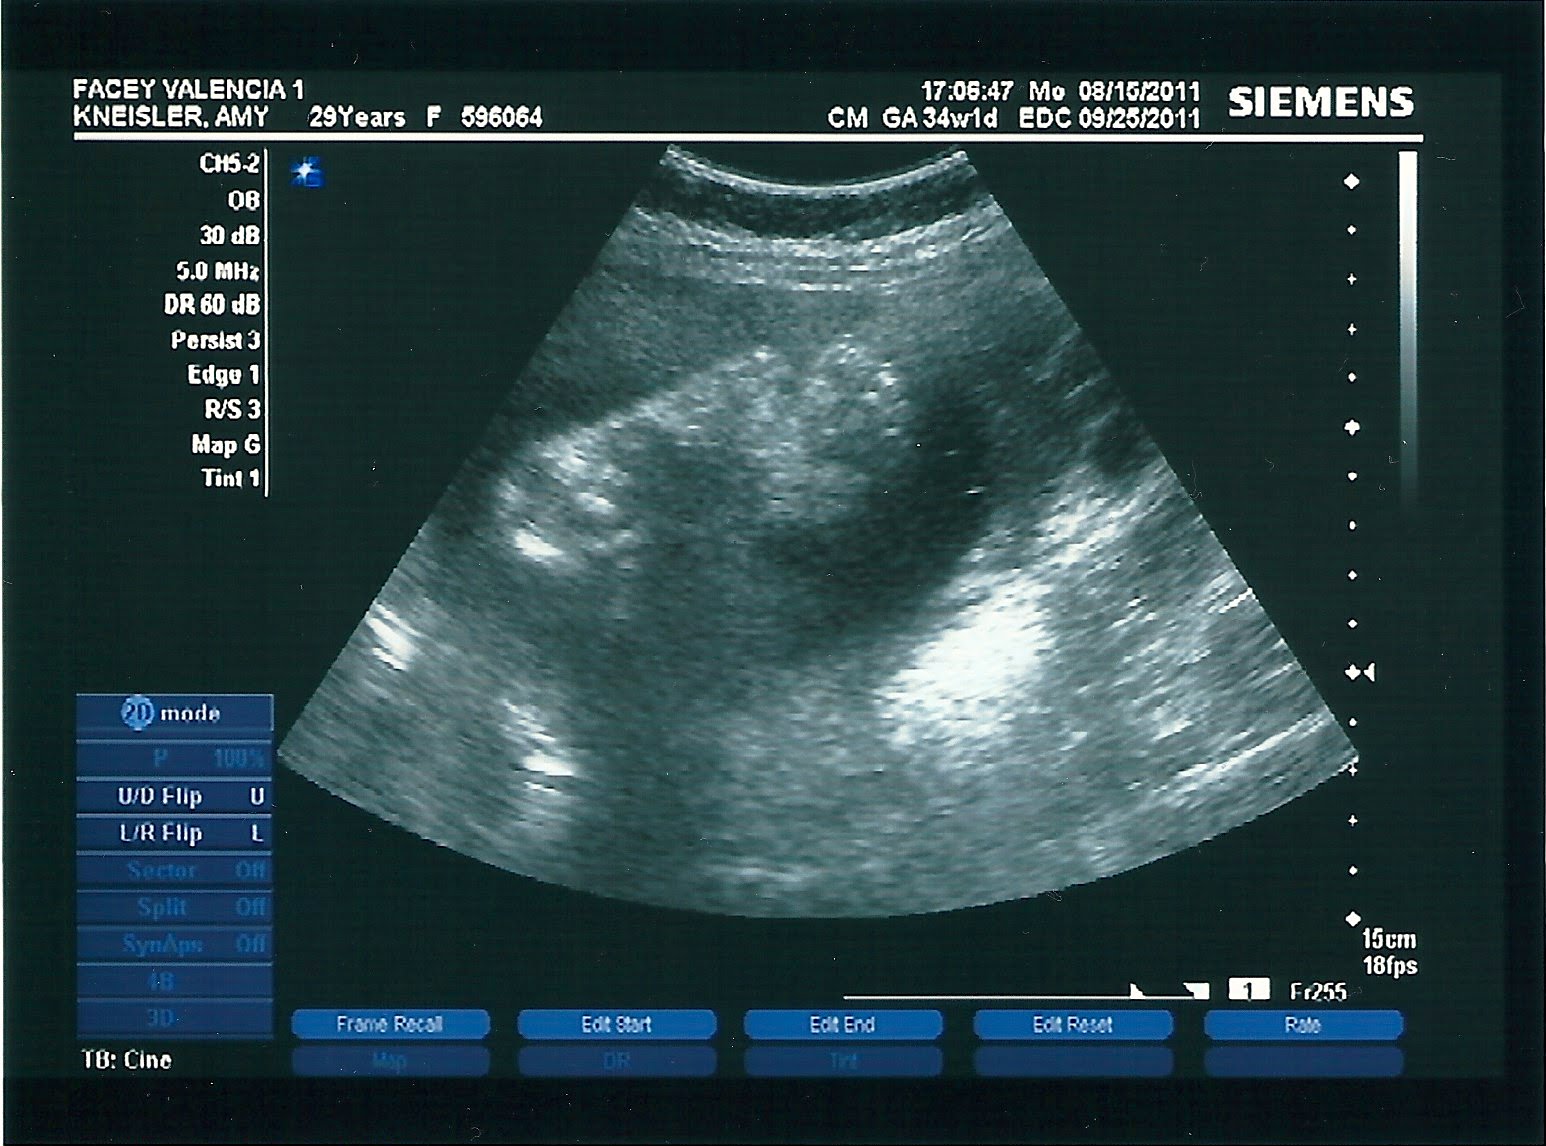

we are officially on baby watch at this point.

the last three office appointments i’ve had external measurements that were 2-4 weeks bigger than my actual gestational size. in non-pregnant people terms…i’m huge and there had to be a reason.

thus, we got an ultrasound!! i love seeing those pictures and hearing that heartbeat!!! my ultrasound tech ended up being a former parent at the daycare i worked for long ago, so i got to see so much more than just measurements.

see those two feet…they are in poking my side at all times.

can’t wait to kiss them.

so, the results, little girl is measuring 2 weeks ahead and my due date is being moved up to sept. 9th from the 25th. that put’s me into crazy-pregnant-lady-nesting mode. i should have the nursery completed by next week and will do a big post all about it!!